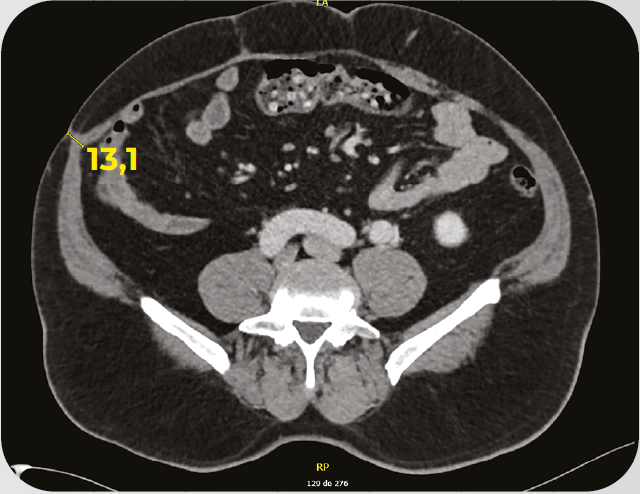

Caso clínico: paciente com CRC MSI-H O Caso clínico em questão, traz detalhes sobre o tratamento em 1L de pacientes com câncer colorretal metastático com deficiência de enzimas do reparo (dMMR)/alto nível de instabilidade de microssatélites (MSI-H).